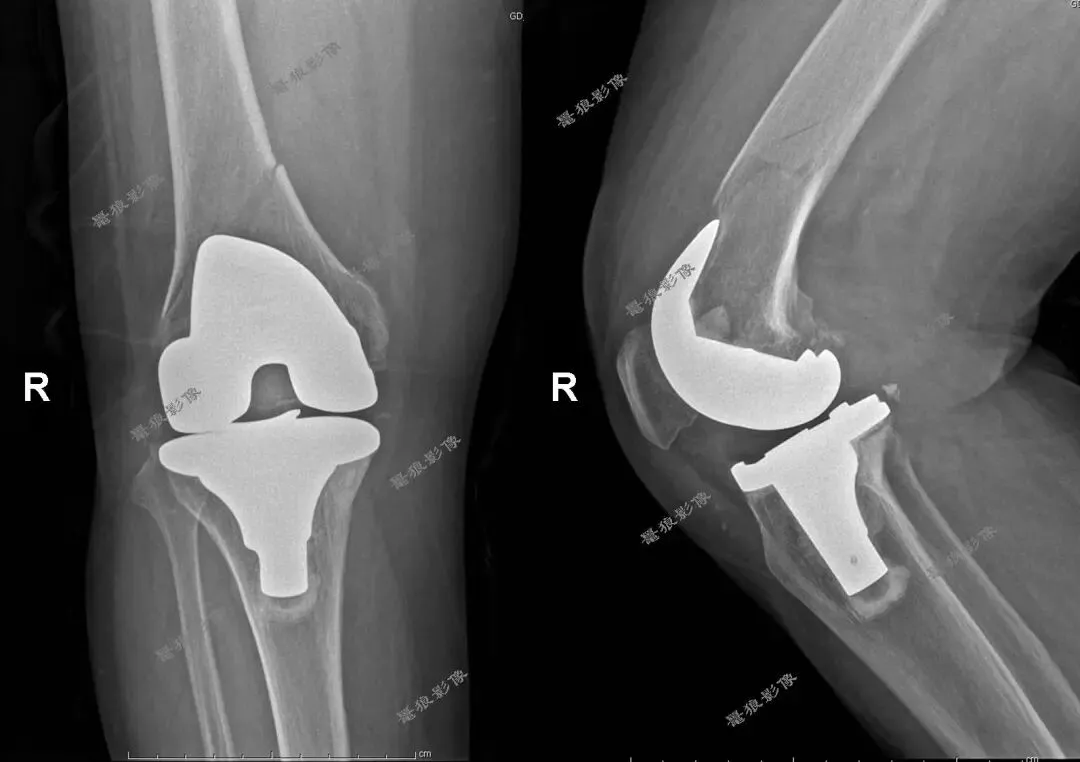

术后: